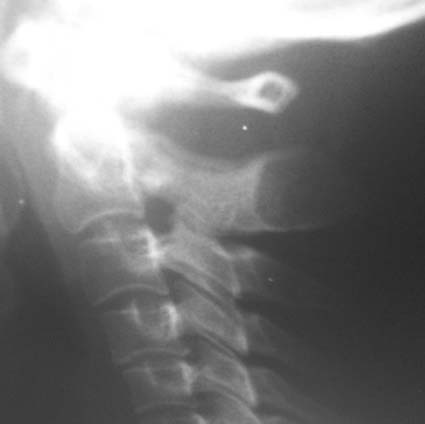

女,45岁,近来感颈部疼痛,头晕,夜不能寐,按之枢椎棘突,感有硬结感,疼痛,骨科怀疑骨囊肿,拟手术,请大家帮忙看一下,是否是正常的?

颈椎骨质增生;颈4/5、5/6椎间盘变性,未除突出,建议mr颈椎检查。

楼主所指的枢椎棘突密度减低区属正常表现,你可能多拿几个颈椎侧位片看看。

下面是我刚从网上下载的几张颈椎图片。

生理曲度变直